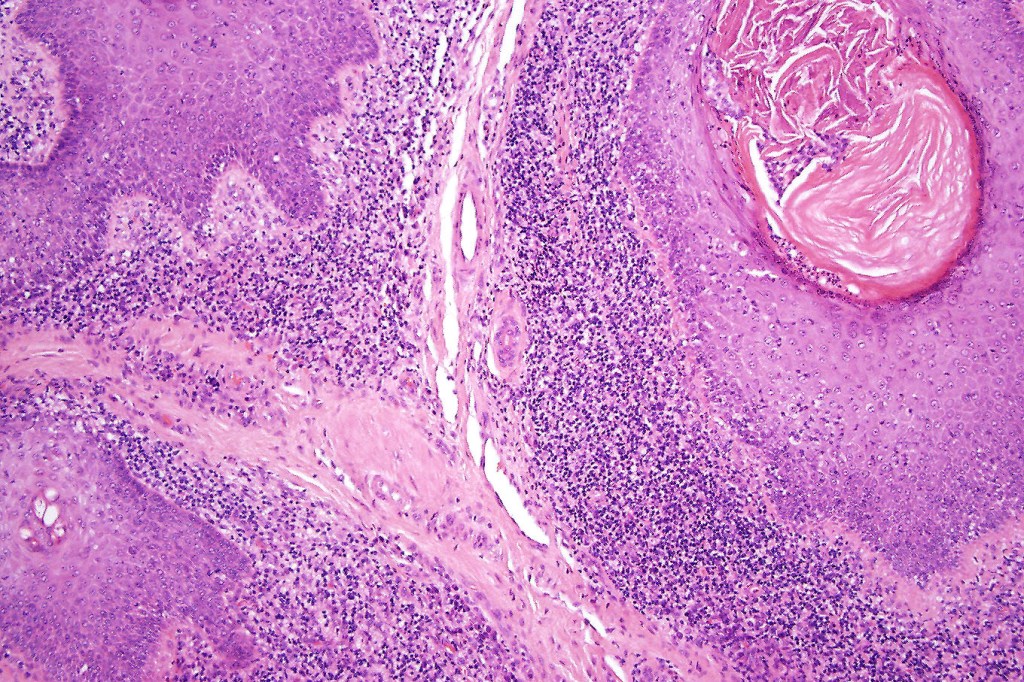

Histological features

•Follicular infiltration by atypical lymphocytes & Sézary cells

•+/- basaloid follicular hyperplasia

•Granulomatous inflammation secondary to follicular destruction

•Large cell transformation occasionally present